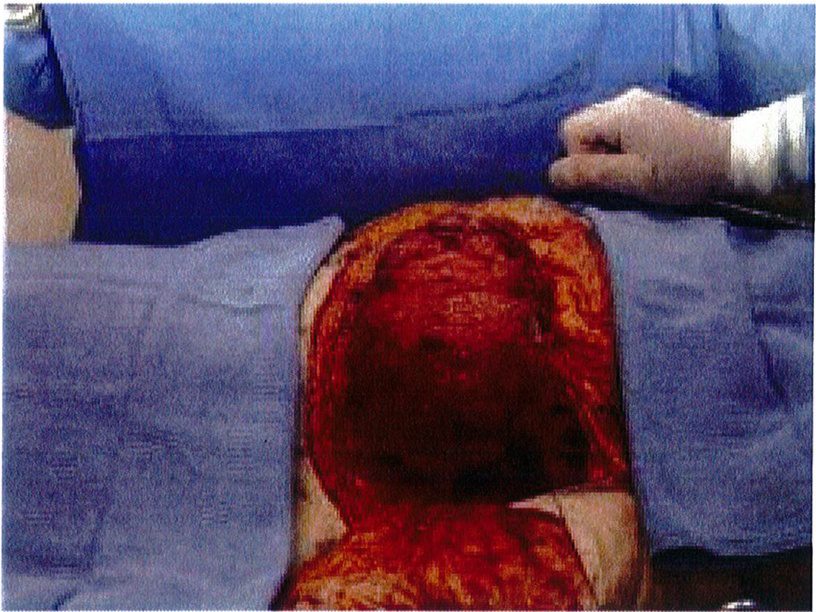

Hệ thống cân nông có thế được đánh dấu sau khi đã bộc lộ để xác định dễ dàng hơn, đồng thời các đường khâu cũng chính xác hơn. Sau đó dùng chỉ Mersilene số 1 khâu lớp cân nông lại với nhau và siết chặt chỉ để tạo thành một khối hình cầu (Hình 6). Kết quả thu được sẽ tương tự như khi bệnh nhân được đặt một khối implant cỡ lớn, với điểm hình chiếu tốt (Hình 7). Sau đó chúng được neo vào lớp cân nông phía trong (cạnh xương cùng) đã được bảo tôn trước đó. Lúc này có thể dùng chỉ Mersiline 3 (Hình 8). Cho tới nay không ghi nhận một trường hợp ứ máu hay tắc nghẽn ở tĩnh mạch vùng mô trung tâm nào.

Một túi bao bọc mô trung tâm được tạo ra dựa trên kích thước vùng vừa khâu purse-string. Túi này được đính ngang với lớp cân nông vùng mông (Hình 9). Chúng sẽ được kiểm tra thường xuyên để luôn ôm sát khối mô trung tâm.

Hình. 9. Một túi được tạo ra theo đúng kích thước phần mô trung tâm đã khâu lại. Điều đặc biệt là chúng được làm từ chính tổ chức dưới da vừa khử biểu mô của mô trung tâm.